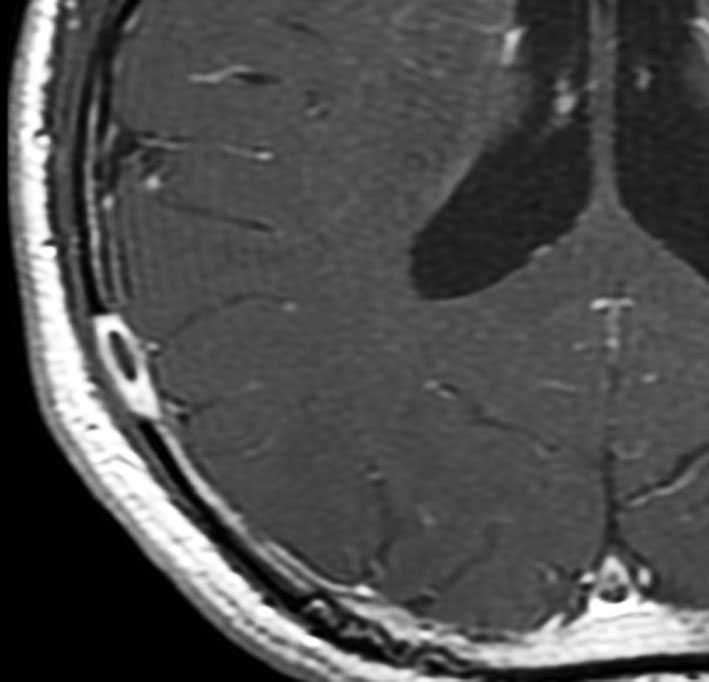

9歳の男の子です。右側頭部が腫れてきたのに気づきました。頭蓋骨のいびつな破壊像があります。

左はMRI T2強調画像です。まるで丸い腫瘍のように見えます。

下のT1強調画像では,ガドリニウム造影剤で強く増強されていて皮下に炎症性腫脹がみられ,活動期の病変であるのがわかります。

この病変は単発(孤発)病変ですが,ややいびつな形をしていて,頭皮の方に盛り上がっていますから,活動性の病変です。手術で完全摘出すると治りますから,骨欠損が広がるようなら手術したほうがいいです。理由は,手術が簡単なこと,病理診断がつくこと,これ以上の病変の広がりを抑えることです。最近は自然の骨に近いような人工骨で補填することができますが,骨形成しなくても自然修復で骨形成されます。とくに,低年齢児では骨形成をしない時もあります,頭蓋骨が自然再生するからです。